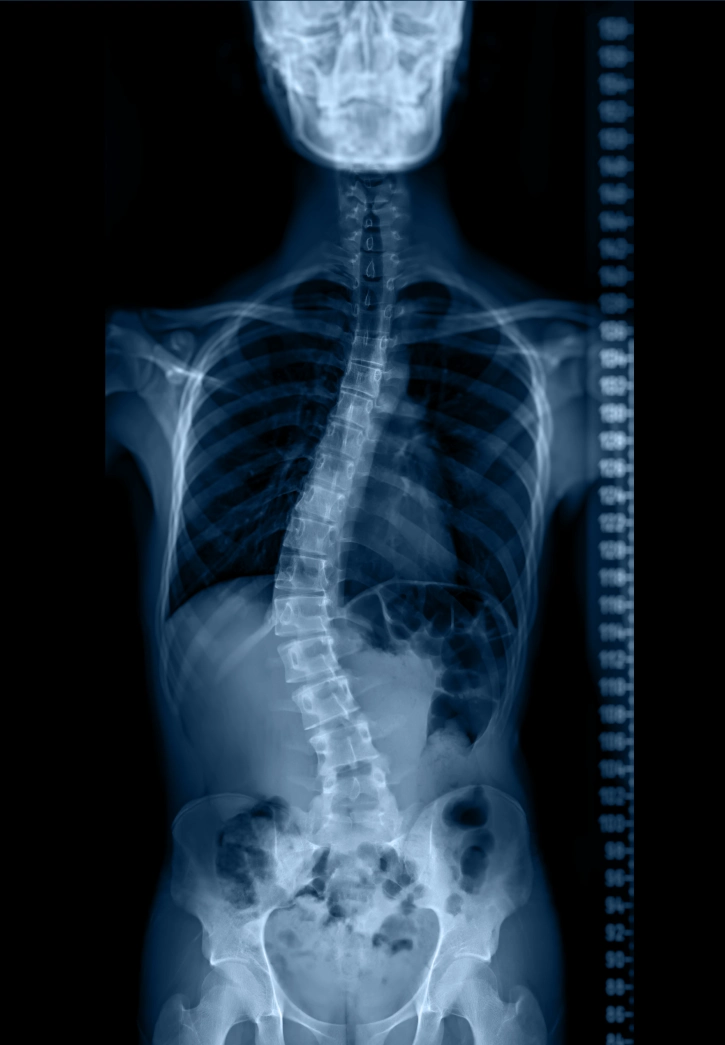

Scoliosis is an abnormal sideways curvature of the spine, often forming an “S” or “C” shape when viewed from behind. While mild curves may cause few symptoms, more significant curvature can affect posture, balance, and nerve function.

- X-rays to measure curve degree (Cobb angle)